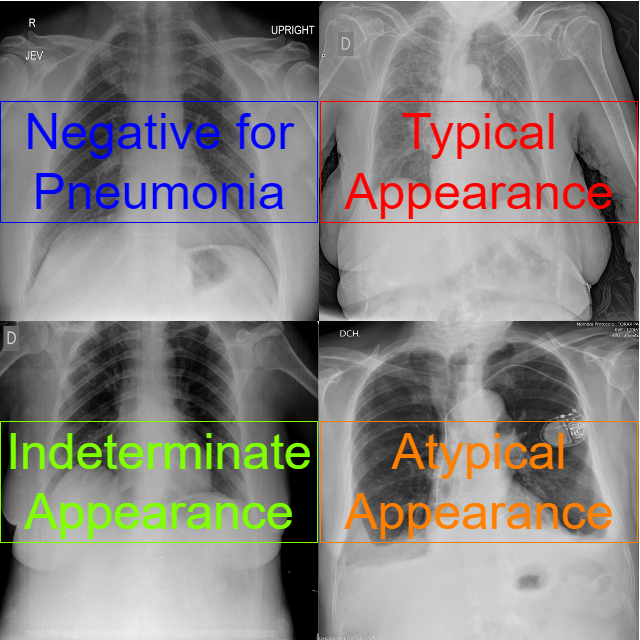

Identification and localization COVID-19 abnormalities on chest radiographsVan Tien Pham and Thanh Phuong NguyenIn The International Conference on Artificial Intelligence and Computer Vision, 2023Solutions to screen and diagnose positive patients for the SARS-CoV-2 promptly and efficiently are critical in the context of the COVID-19 pandemic’s complex evolution. Recent researches have demonstrated the efficiency of deep learning and particularly convolutional neural networks (CNNs) in classifying and detecting lung disease-related lesions from radiographs. This paper presents a solution using ensemble learning techniques on advanced CNNs to classify as well as localize COVID-19-related abnormalities in radiographs. Two classifiers including EfficientNetV2 and NFNet are combined with three detectors, DETR, Yolov7 and EfficientDet. Along with gathering and training the model on a large number of datasets, image augmentation and cross validation are also addressed. Since then, this study has shown promising results and has received excellent marks in the Society for Imaging Informatics in Medicine’s competition. The analysis in model selection for the trade-off between speed and accuracy is also given.